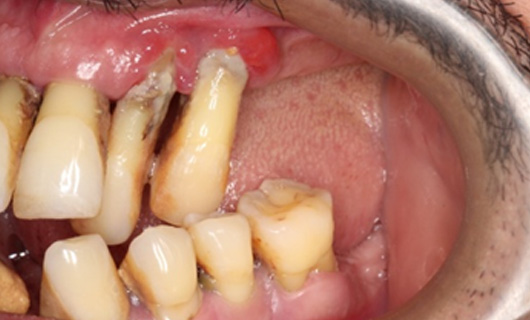

- Impressions: After your gums are substantially healed and healthy, your dental assistant or dentist will make an impression of jaws.

In the absence of tooth roots, the jawbone will shrink unless it is stimulated in another way. A dental implant prevents residual bone loss maintaining the jaw dimensions thus increasing its durability.

- Preserves gum tissues and bone